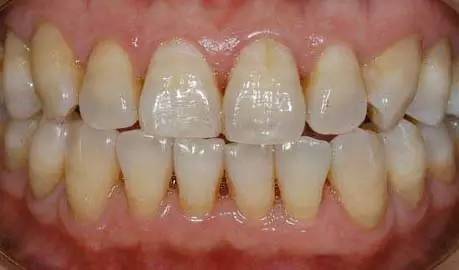

很多人觉得刷牙只不过是一件小事情,其实不然。现在,请你先对照镜子,张开嘴,看看你的牙齿根部,是不是像下图一样,隐隐约约有些凹下去了?如果是,那你就得当心了!

与普通蛀牙不同,出现这种情况,你的牙齿危险了!医学上称之为“楔状缺损”!

这种横槽就是“楔状缺失”!由于它外形酷似木匠用的楔子,因此称为“楔状缺损”。

楔状缺损是发生在牙齿唇、颊面颈部的慢性硬组织缺损,呈“V”状,由于它的外形酷似木匠用的楔子,因而得名楔状缺损。多见于前牙或者双尖牙的唇面,以中老年患者居多。

温馨提示:其实当你感觉到牙齿不适、酸痛等症状时,问题已经相当严重了。平时我们可以做下自检:对着镜子,看看牙齿颈部有没有小的缺损。